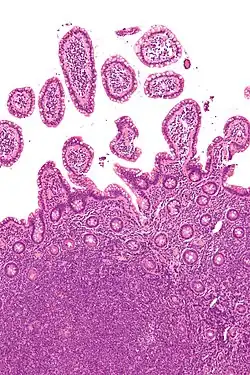

| Micrograph of mantle cell lymphoma, a type of non-Hodgkin lymphoma. Terminal ileum. H&E stain. | |